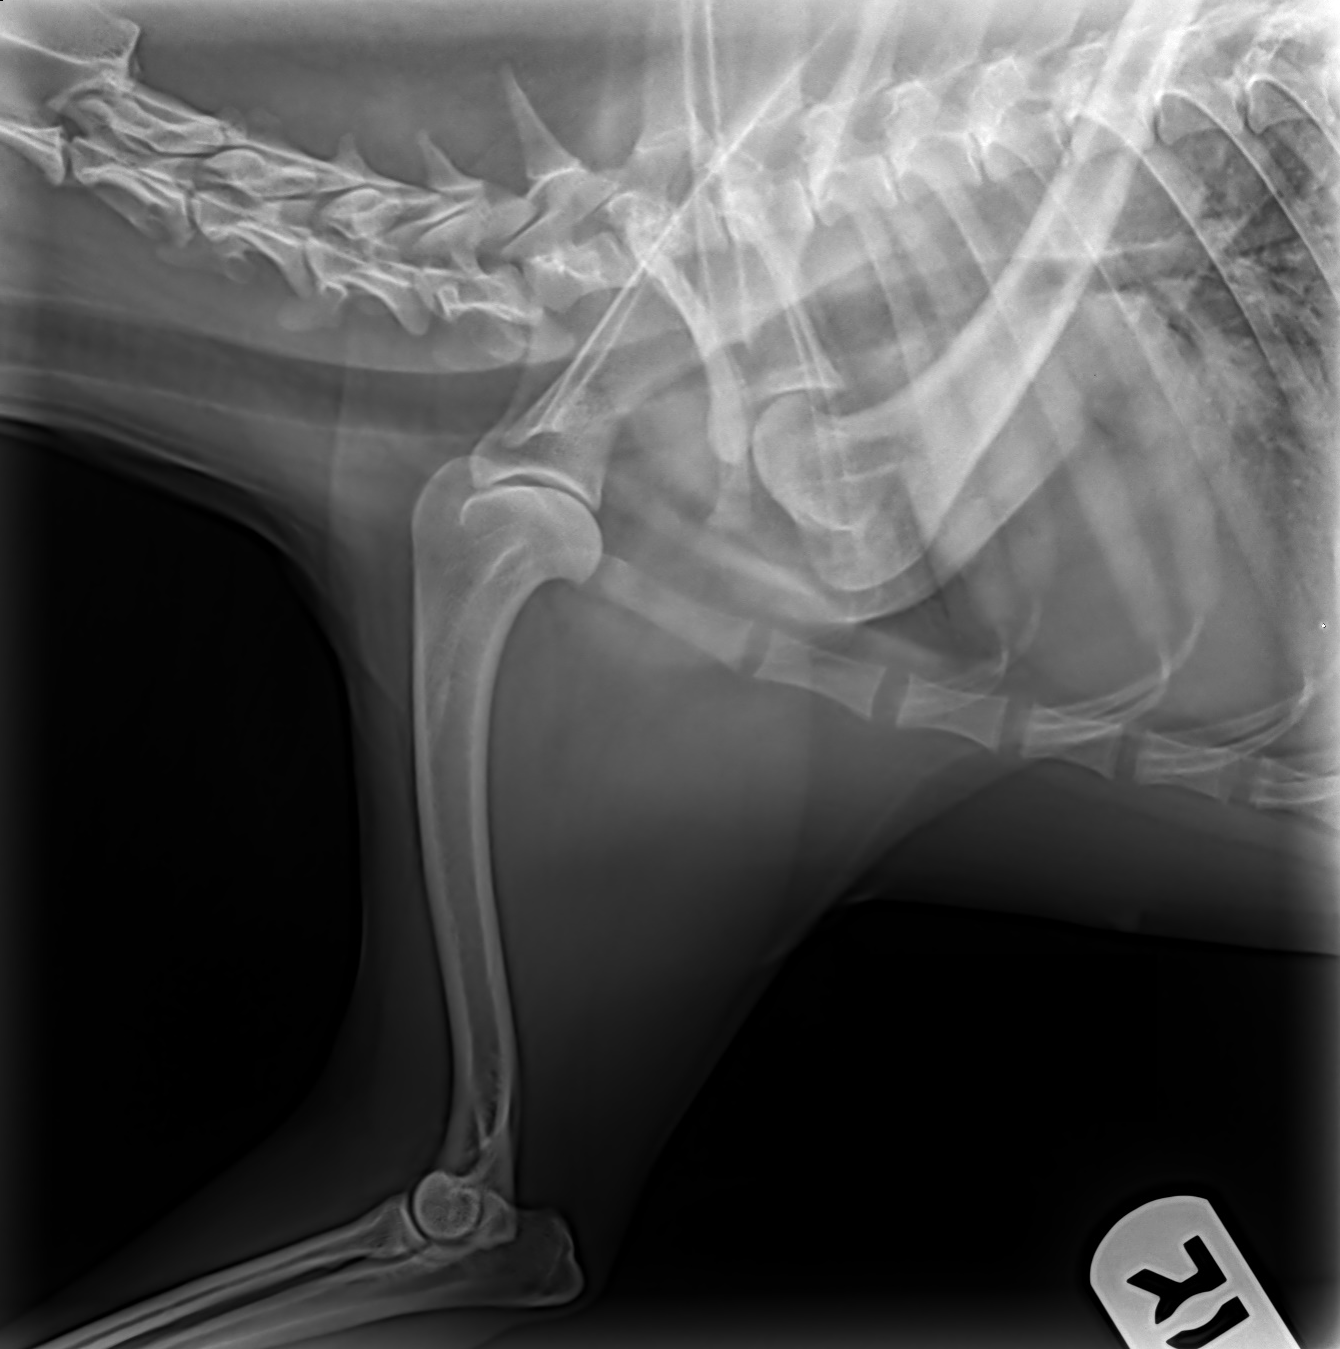

ofa | pelvis

rating | good

pennhip

right di 0.41 | left di 0.34